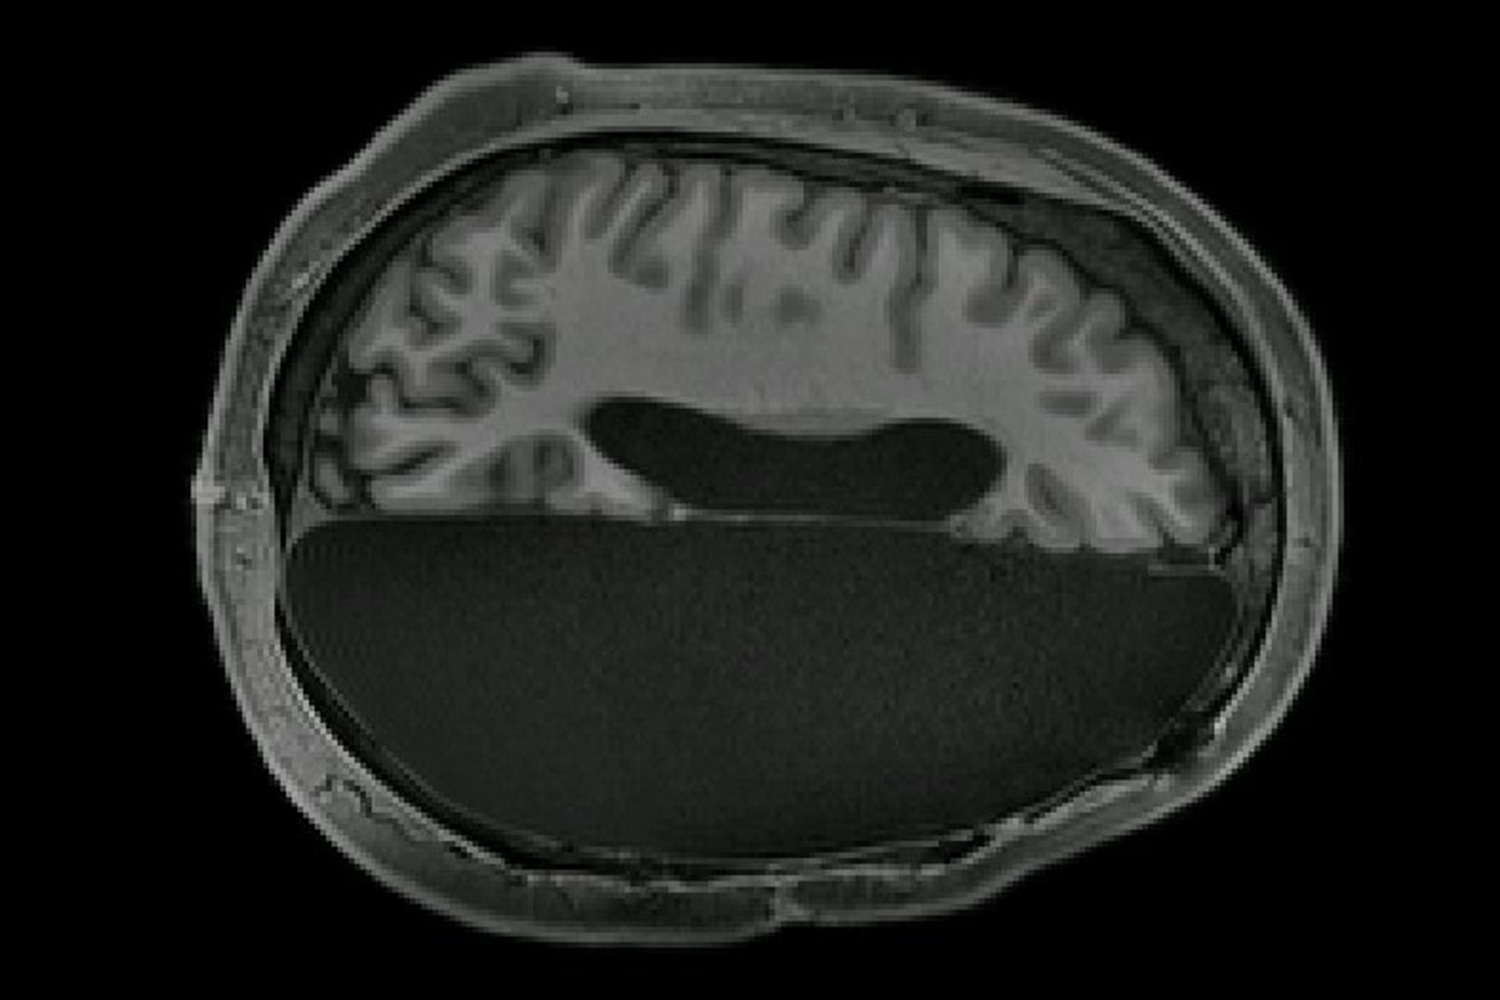

17. Introvert and extrovert brains physically differ

Image source/Ongig BlogSomething really fascinating has shown up from MRI scans that suggests that introverts and extroverts have measurable physical changes in their brains. The brain of the extrovert showed a far more active dopamine reward network, whereas in the introvert's brain, more grey matter was present.